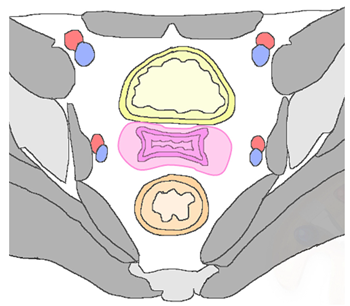

- 1.

- Local or central-pelvic (including recurrence in the vaginal vault alone, cervix, uterus, parametria);

- 2.

- Regional (with or without vaginal involvement) defined as anterior, invading bladder, ureters, urethra, or as posterior, invading rectum, anal sphincter, or as lateral, invading pelvic side wall, vessels and nerves, or involving pelvic lymph nodes stations;

- 3.

- Distant, including infra-diaphragmatic (para-aortic lymph nodes) or supra-diaphragmatic nodal recurrence, or distant organ metastasis (lungs, liver) [4].